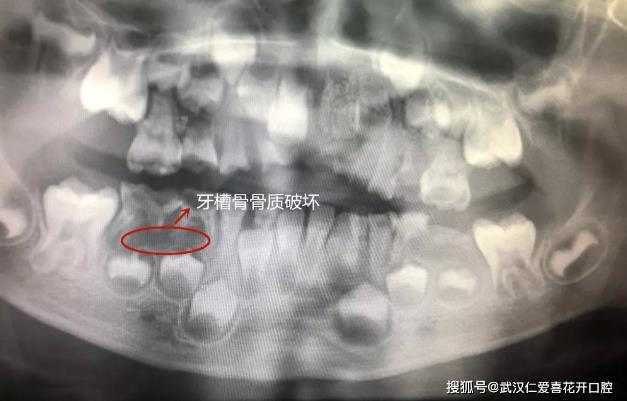

經檢查發現,瑞瑞的口腔狀況不容樂觀。20顆牙齒中,有2顆深齲,有11顆牙齒僅剩殘冠,牙根完全吸收。還波及到繼承恒牙胚的發育、礦化,鈣化,會導致日后新牙萌出后會出現發育不全發育異常等情況。此外,瑞瑞右下有2顆牙齒有嚴重根尖炎癥,造成牙槽骨骨質破壞,如果不盡早處理,這個骨質破壞會繼續下去,可能會導致頜骨間隙出現感染,引起頜骨的骨髓炎。

(紅色區域為牙槽骨骨質破壞區)